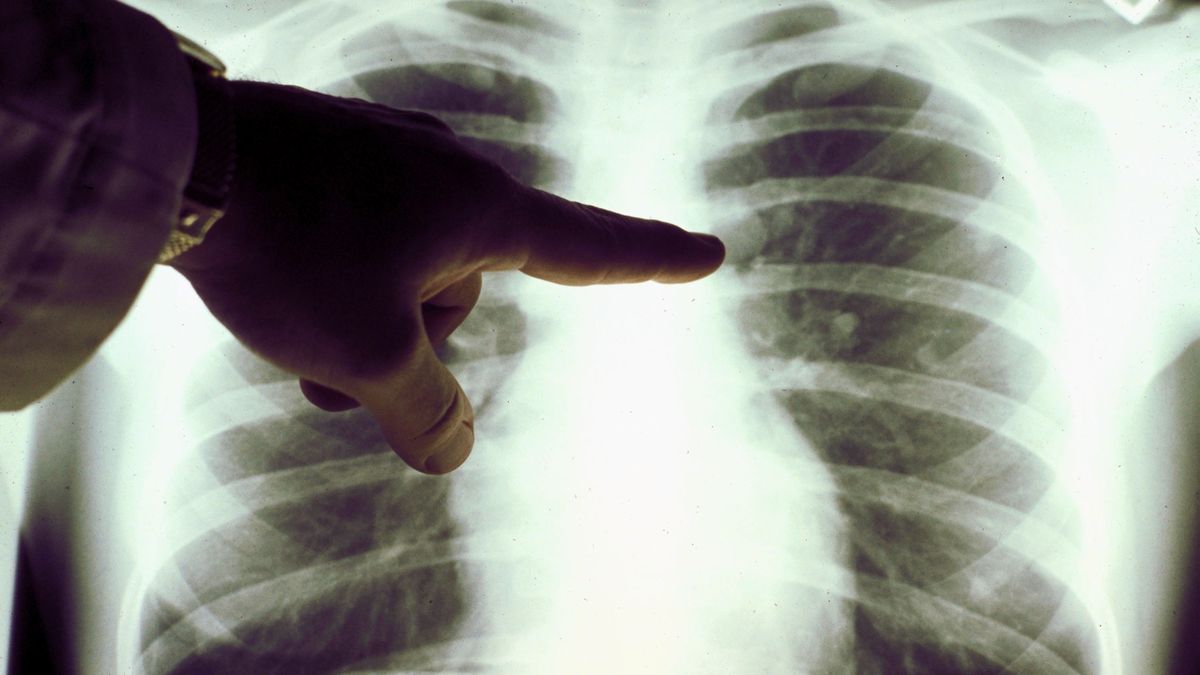

Nowotwory wciąż są jedną z najczęstszych przyczyn zgonu w Polsce i Europie. Prognozy opracowane przez European Cancer Information System (ECIS) dla Komisji Europejskiej, wskazywały, że w 2020 roku, w samej tylko Polsce, na nowotwory złośliwe zachoruje niemal ponad 196 tys. osób. W związku z tym Komisja Europejska ogłosiła "europejski plan walki z rakiem". Dużą rolę w programie odgrywa Polak - Bartosz Arłukowicz.